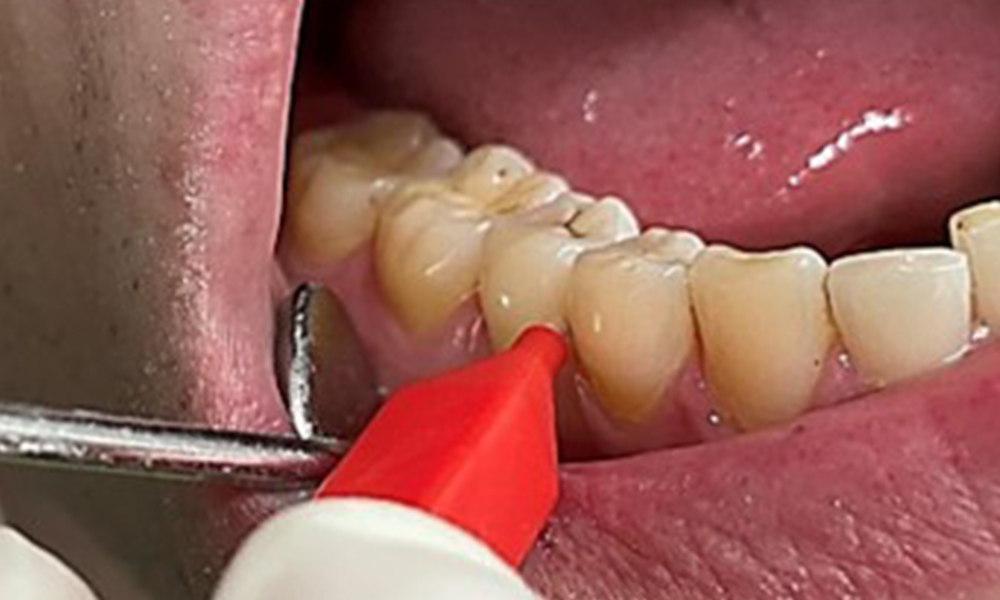

În contextul stării clinice generale favorabile, necesarul de măsuri individuale, ce urmează a fi determinat în cursul examinării intraorale, va avea un rol deosebit de important în planul de tratament. Va fi esențială determinarea periodică a profunzimilor de sondare. Sângerarea gingivală se diminuează la fumători, motiv pentru care diagnosticul clinic de parodontoză nu poate fi pus decât prin sondare (fig. 7). Punerea accentului exclusiv pe determinarea indicilor de sângerare poate masca prezența bolii parodontale și/sau a gingivitei existente. (5)

Situația parodontală necesită examinare amănunțită o dată pe an. Iar detectarea plăcii bacteriene cu ajutorul unui indicator de placă cromatic poate constitui un factor motivant. Analiza minuțioasă și în conjucție a tuturor rezultatelor examinărilor orale, a suprafețelor bucale și mucoasei linguale este deosebit de importantă la fumători, întrucât aceasta va facilita depistarea timpurie a oricăror modificări morfopatologice (6).